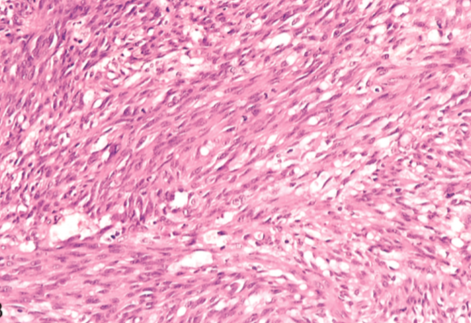

Non ossyfying fibroma

In the lesion we can recognize that is made completely by fibroblasts, we cannot see any osteoid!